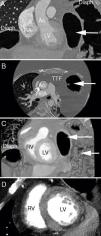

Cardiac computed tomography. (A) Coronal plane with marked herniation of the abdominal contents into the left hemithorax (white arrow); (B) the corresponding axial plane with bowel loops extending up into the thorax to the level of the main pulmonary artery; (C) coronal volume-rendered image of the bilateral diaphragmatic elevation and bowel loops within the thoracic cavity; (D) contrast-filled cardiac chambers with a thin and hypoperfused inferior wall, as typically seen in Duchenne muscular dystrophy. Ao: aorta; Diaph: diaphragm; LV: left ventricle; RA: right atrium; RPA: right pulmonary artery; RV: right ventricle; TTF: transthoracic fat.

For further investigation, alternative imaging was sought. Cardiac magnetic resonance imaging was not feasible owing to body habitus, orthopnea and requirement for continuous non-invasive ventilation. Therefore, a retrospective ECG-gated cardiac computed tomography (CT) scan was performed for functional imaging. This showed mildly reduced LV systolic function with left ventricular ejection fraction of 47%, end-diastolic volume of 147 ml and end-systolic volume of 77 ml. The basal and mid inferior wall appeared thin and hypokinetic with a corresponding hypoperfusion pattern seen on first-pass perfusion imaging typical of Xp21 dystrophies (Figure 1).4 Note was also made of severe herniation of the abdominal contents into the left hemithorax (Figure 1), accounting for the non-diagnostic echocardiogram and contrast echocardiogram studies. The left lung was almost completely collapsed with a minimally aerated left lower lobe and a small amount of aerated left upper lobe as a result of marked elevation of the left hemidiaphragm. There was herniation of the stomach and small and large bowel as well as the tail of the pancreas into the left thoracic cavity. In short-axis view of the left ventricle, the herniated bowel loops gave the appearance of the Olympic rings (hitherto termed the “Kapetanakis-Rajani” sign) (Figure 2).